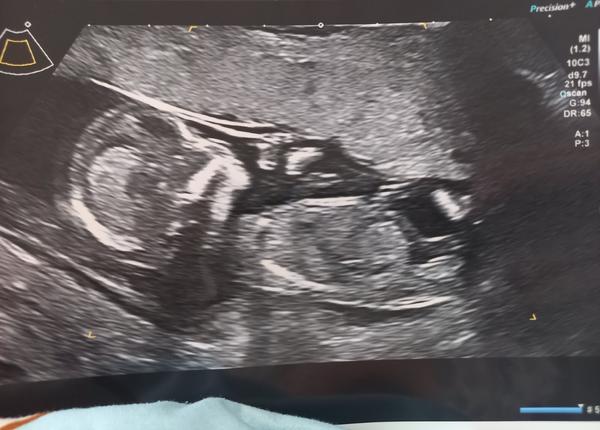

@misiatko69 a co u mne? 😅

@simonabaa holčičku

@adrizojka holčičku

Tak nakonec chlapeček to bude 😁